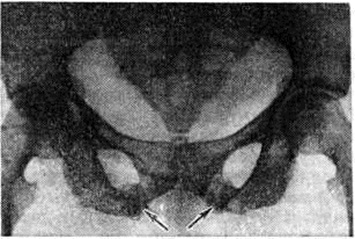

Увеличение количества и толщины костных трабекул при Остеопатия нефрогенная обусловливает рентгенологическую картину остеосклероза. Прежде всего это наблюдается в телах позвонков, где плотные полосы чередуются с более прозрачными. Остеосклероз можно отметить также в рёбрах, черепе и трубчатых костях. Одним из рентгенологических проявлений остеомаляции являются зоны перестройки костной ткани (зоны Лоозера). На снимке они видны как перпендикулярные к корковому слою светлые полосы, напоминающие перелом. Зоны перестройки можно обнаружить в ключице, костях таза (рисунок 3) и длинных трубчатых костях. Остеомаляция может привести к деформации вертлужной впадины. У некоторых больных, долгое время леченных гемодиализом, уменьшается масса костной ткани и появляются переломы. Вторичный гиперпаратиреоз может дать картину фиброзного остеита с очаговым уплотнением кости. Наряду с резорбцией кости происходит образование новой кости. Это наблюдается главным образом у больных, длительно леченных гемодиализом. Периостальное образование новой кости имеет вид тонкой пластинки, отделённой от периоста. У больных после пересадки почки и длительно леченных гемодиализом может наблюдаться остеонекроз (рисунок 4). Степень минерализации костей может быть определена прижизненно методом рентгеноденситометрии (смотри полный свод знаний).